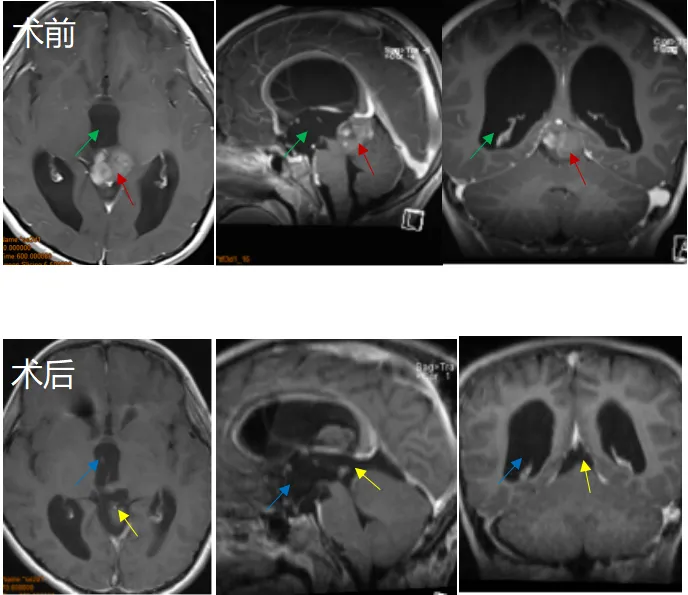

26岁女性,阵发性复视,进行性左外展神经麻痹,MRI显示斜坡巨大脊索瘤,病变浸润性生长,肿瘤延伸浸润至乙状窦(SS)、左侧海绵窦(CS)、下斜坡到脑干脚间池硬膜部分(图A、B)。

该名女士找到INC福教授进行手术,第一期手术,福教授采用联合内镜鼻内入路(EEA)切除硬膜外部分重量,对于硬膜内部分肿瘤采用经颅入路,以降低脑脊液漏和神经血管损伤的风险。

首先,进行内镜鼻内活检,显示典型的脊索瘤。然后,她接受了内镜经鼻入路手术,从硬膜外部分切除到斜坡和海绵窦部分的肿瘤(图C、D)。

2个月后,进行第二次手术,使用右侧mini经岩骨入路切除硬膜内肿瘤。术后MRI显示肿瘤完全切除GTR(图E、F)。术后接受了质子束治疗(PBT)。5个月随访时,她的神经系统检查正常,头面部外观美容效果也非常好。